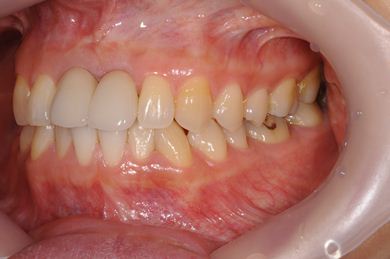

| 治療方針 | 上顎前歯、抜歯と同時にインプラントを埋入し、治療期間を短縮する。 | ||||||||||||||||||||||||||||||||

| 治療内容 | インプラント2本、メタルボンドセラミッククラウン2本 | ||||||||||||||||||||||||||||||||